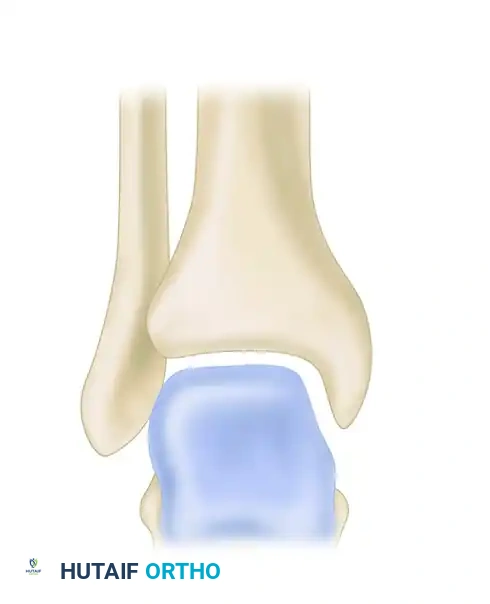

Biomechanical Pearl: The fundamental principle guiding all ankle trauma surgery was established by Ramsey and Hamilton, who demonstrated that a mere 1-mm lateral shift of the talus within the mortise produces a 42% reduction in the tibiotalar contact area. Because stress per unit area increases exponentially as the total contact area decreases, even microscopic displacement contributes to poor functional outcomes and accelerated articular degradation.

Radiographic Relationships

Accurate interpretation of standard radiographs remains the cornerstone of initial evaluation. The relationships evaluating the tibiofibular articulation are critical for diagnosing subtle diastasis.

FIGURE 89-7: Radiographic relationships important in evaluating the tibiofibular articulation. Line EF represents the medial clear space; line AB represents the tibiofibular clear space.